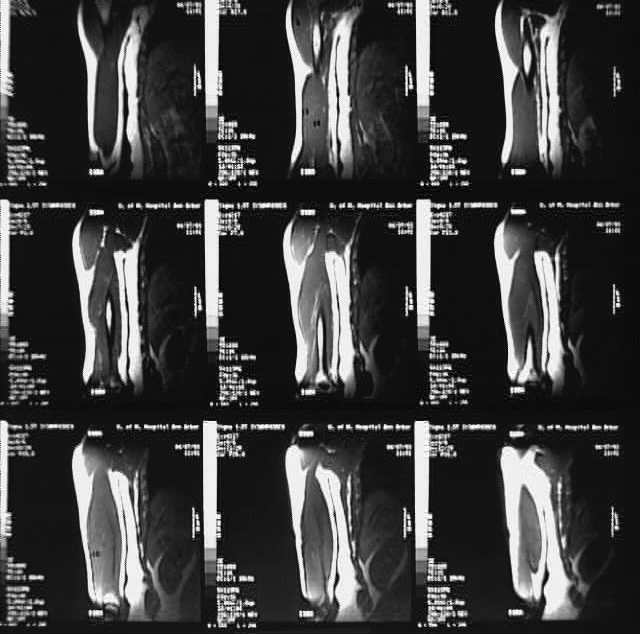

Radiology Images

Upper Limbs: Arm MRI Coronal: